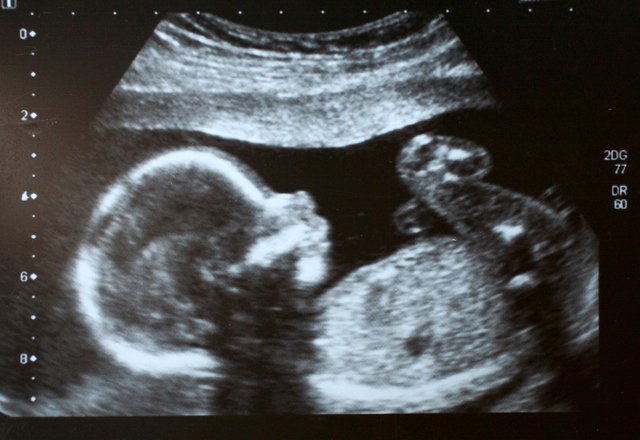

Araştırmacılar, hamile kadınlara önce havuç sonra lahana kapsülü verdi ve bebeklerin tepkilerini 4D ultrasonla izledi.

Havuç aromasına maruz kalan bebekler daha fazla “kahkaha surat” tepkileri verirken, lahana aromasına maruz kalanlar daha fazla “ağlayan yüz” tepkileri gösterdi.

İnsanlar; tat ve doku kombinasyonu ile lezzeti deneyimlerken, doğmamış bebekler; amniyotik sıvının solunması ve yutulması yoluyla lezzet alabiliyor.